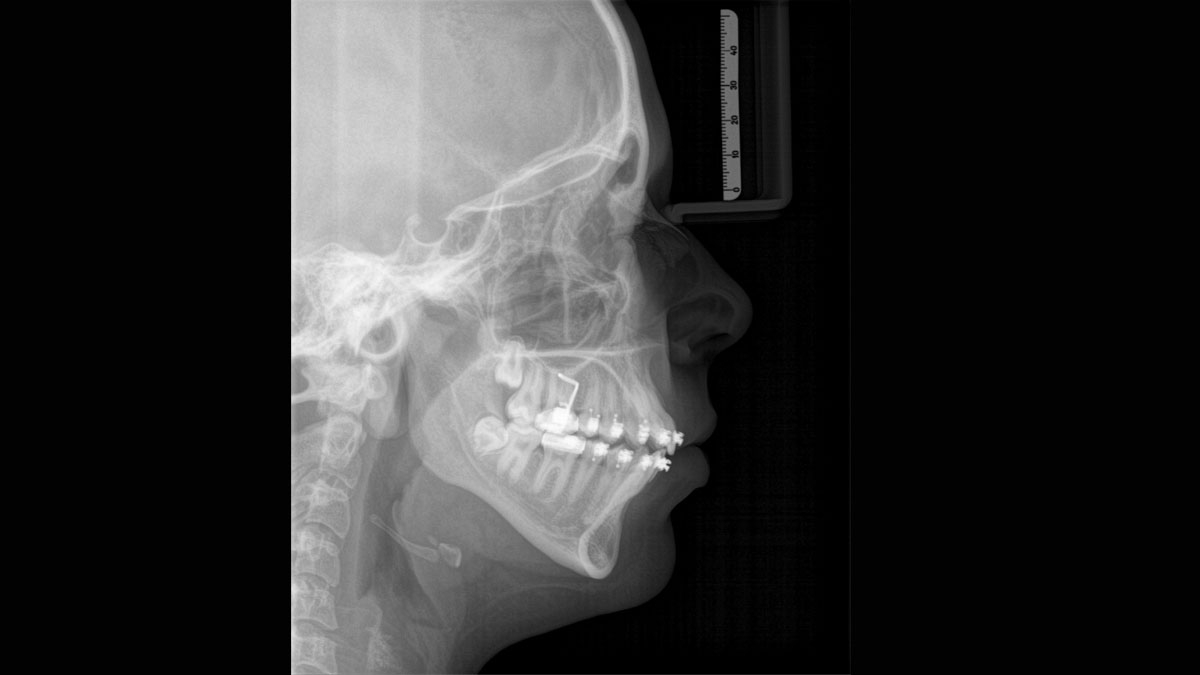

PIA (Patient Positioning & Image Assistant) je 10bodový koncept pro snadné polohování pacienta a rentgenové zobrazování a je především o dvou věcech: vysoké kvalitě snímků a komfortu pro pacienta a obsluhu rentgenu. PIA poskytuje podporu a zajišťuje nástroje pro zhotovení vysoce kvalitních snímků, potřebných pro analýzu léčby. Je zaměřen na ergonomii a komfort pacienta i obsluhy rentgenu. Patentovaný skusový blok automaticky zajistí správné naklonění hlavy, umístění pacienta v okluzní rovině, a spolu s 3bodovou fixací hlavy a pevnými madly pro stabilní polohu pacienta omezuje potřebu nežádoucích korekčních skenů.